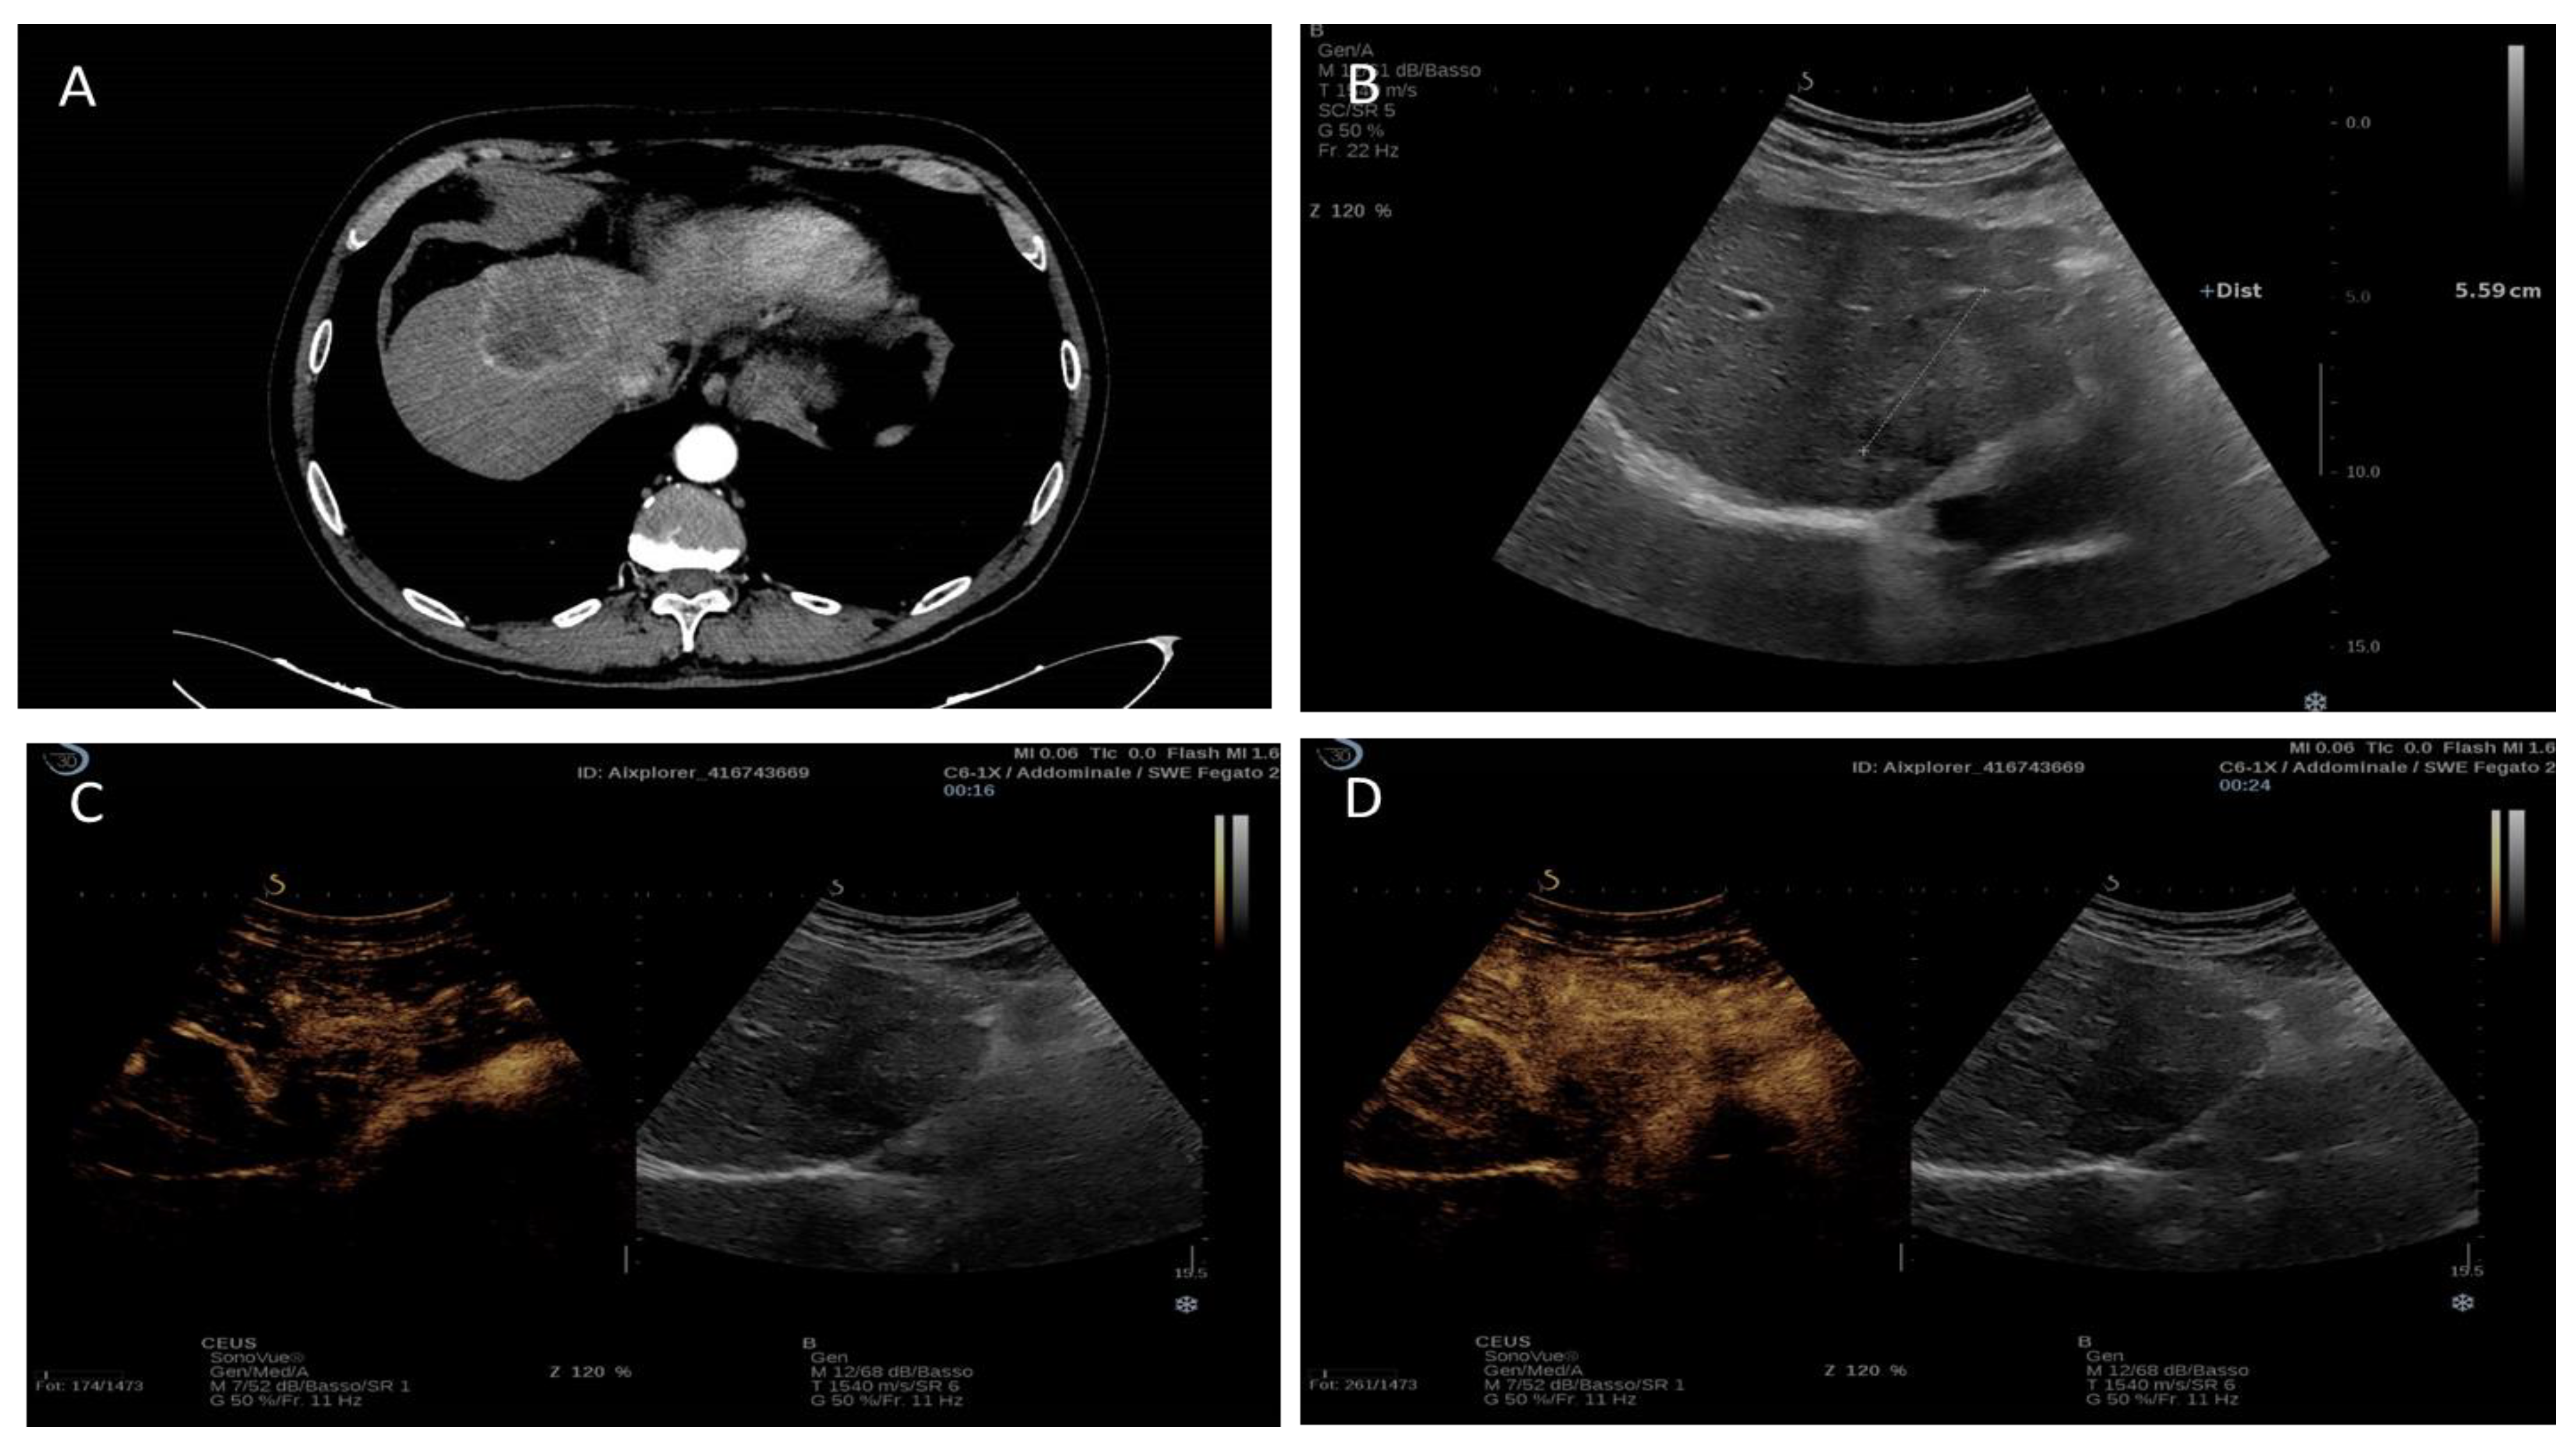

Figure 5.

Contrast-enhanced imaging features a lesion of 5.5 cm intrahepatic cholangiocarcinoma of segment IV. (A) CT imaging: peripheral hyperenhancement in the arterial phase; (B) Hypoechoic aspect in B-mode ultrasound. (C,D) Contrast-enhanced ultrasound: peripheral hyperenhancement in the arterial phase and subsequently marked early washout.